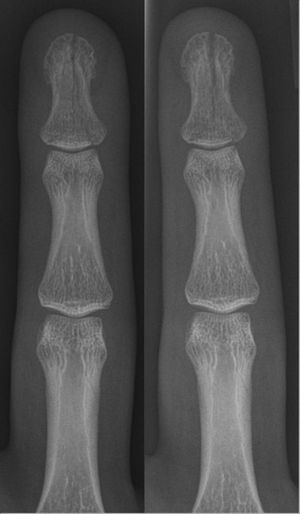

- 손 골절

- 중수골 골절 (복서 골절 포함)

- 엄지손가락 중수골 기저부 골절 (베넷 골절, 롤란도 골절)

- 말렛 골절 (말단골 골절, 골성 망치 수지)

때때로 발가락과 손가락의 말단골과 같은 작은 뼈는 깁스 없이 버디 테이핑으로 치료할 수 있는데, 이는 깁스를 만드는 것과 유사한 기능을 한다. 스즈키 프레임이라는 장치는 깊고 복잡한 관절 내 손가락 골절의 경우에 사용할 수 있다.[40] 제한적인 움직임만 허용함으로써, 고정은 섬유 연골 가골 형성을 가능하게 하면서 해부학적 정렬을 유지하는 데 도움이 되며, 이는 유합(골절된 뼈가 다시 붙는것)을 달성하는 목표로 이어진다.